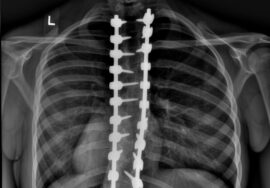

يعاني بعض المراهقين من اعوجاج العمود الفقري، وهو انحناء غير طبيعي للظهر غالبًا يظهر أثناء مرحلة النمو السريع في سن البلوغ. من أشهر طرق العلاج غير الجراحية لهذا الانحناء هو حزام اعوجاج العمود الفقري، الذي يهدف إلى تقليل ومنع زيادة الانحناء وتحسين شكل الظهر.

لكن ليس كل المرضى يحققون نفس النتائج مع الحزام، وهناك عوامل كثيرة تؤثر على فعالية العلاج. فقد أثبتت الدراسات الحديثة أن شكل العمود الفقري والقفص الصدري لكل مراهق يلعب دورًا كبيرًا في نجاح حزام اعوجاج العمود الفقري.

هناك نوعان رئيسيان من شكل القفص الصدري: المائل لأسفل والمستوي أفقيًا. الشكل الأفقي يتيح تصحيح أفضل للانحناء عند استخدام الحزام، خاصة إذا كان دوران الصدر محدودًا.شكل العمود الفقري من الأمام والخلف

بعض المراهقين لديهم شكل العمود الفقري يشبه حرف “S”، والبعض الآخر يشبه حرف “V”. هذه الاختلافات تؤثر على كيفية توزيع الضغط داخل الحزام ومدى قدرته على تصحيح الانحناء.

صور الأشعة والمتابعة الدورية تساعد الطبيب على معرفة مدى تأثير الحزام على الانحناء والتأكد من أن تصميم الحزام يلائم المراهق أثناء النمو.تمارين داعمة للظهر